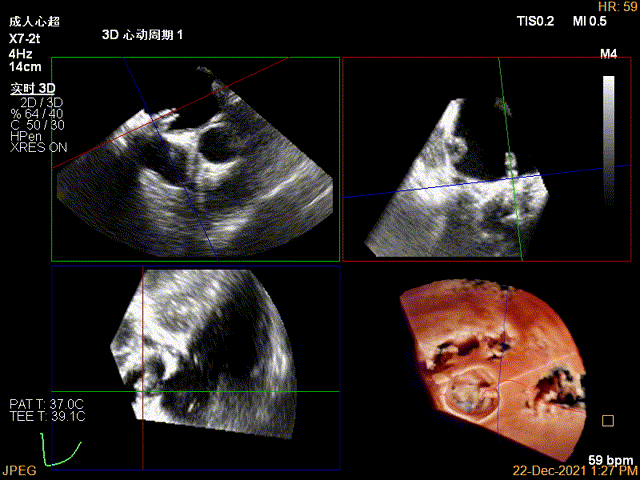

确定房间隔穿刺点:中部靠后

穿刺点高度测量:4.68cm

3D视图穿刺点位近似于3点位

3D视图下大鞘位置及长度测量

2D视图下trajectory

3D视图下开夹子

3D视图下调整夹子位置及Rotate,第一个夹子放置于靠近内侧区域

3D视图下夹子对准最大反流束进入左室